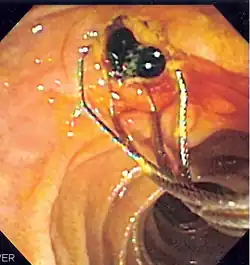

Duodenoscopic image of two black pigment stones extracted from common bile duct after sphincterotomy

When needed, the sphincters of the ampulla and bile ducts can be enlarged by a cut (sphincterotomy) with an electrified wire called a sphincterotome for access into either so that gallstones may be removed or other therapy performed.[10]

Other procedures associated with ERCP include the trawling of the common bile duct with a basket or balloon to remove gallstones and the insertion of a plastic stent to assist the drainage of bile.[11] Also, the pancreatic duct can be cannulated and stents be inserted.